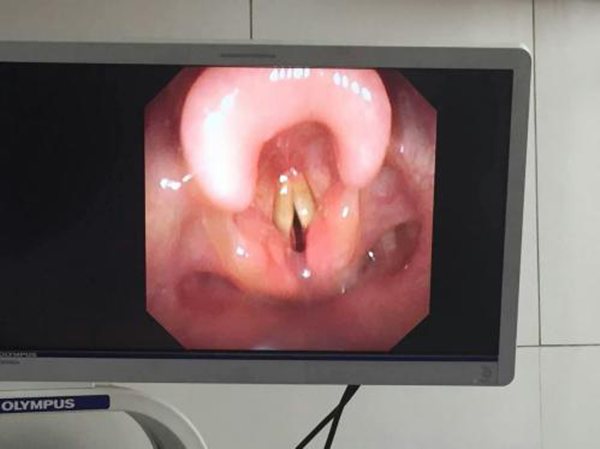

王惠萍副主任立即与耳鼻喉科孙斌副主任认真商讨,详细认真与家属沟通纤维支气管镜操作相关问题,并做好全面术前准备及术中可能出现并发症的防范。孙斌教授在助手协助下,对生后仅8天的小宝宝成功进行了经鼻纤维支气管镜检查,历时数分钟,镜检提示会厌水肿,双声带充血,水肿,声门下粘膜皲裂水肿。当孙教授把纤支镜退出来的那一刻,大家都为这个幼小而又强大的生命松了口气。整个过程宝宝生命体征平稳,术后无不良反应。现一般状况良好,在新生儿科恢复治疗中。